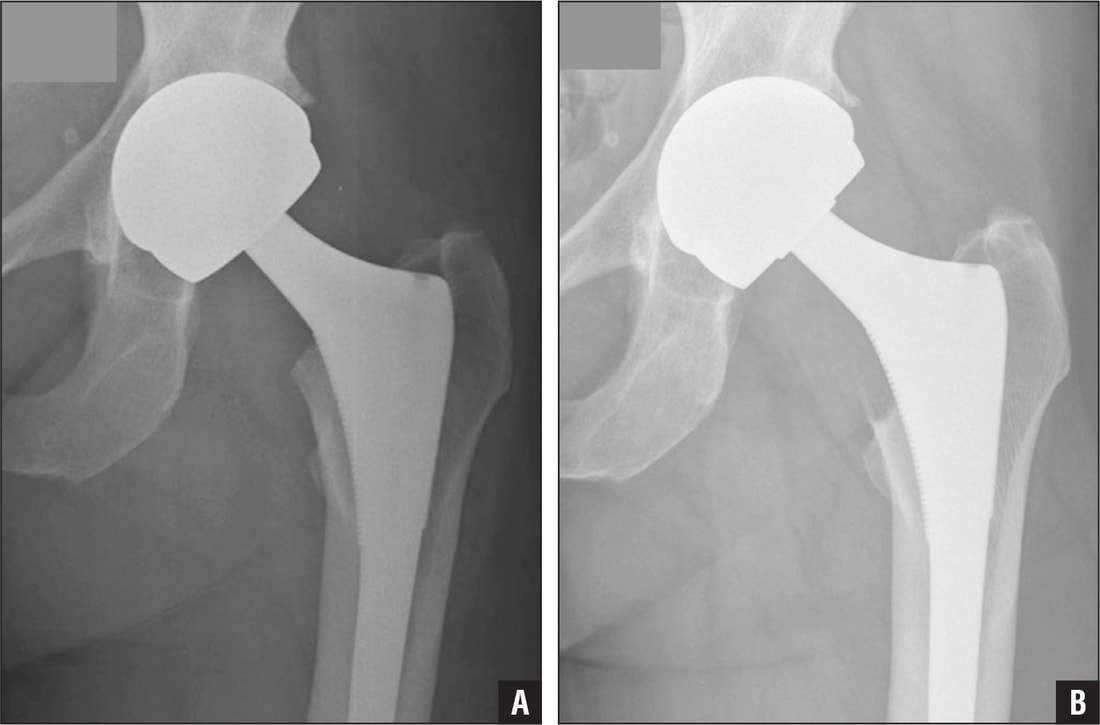

Hip replacement surgery is a procedure in which a surgeon removes damaged sections of the hip joint and replaces them with artificial parts. The hip is a ball-and-socket joint. The ball, at the top of the femur, fits into a rounded socket in the pelvis.

During the surgery, the damaged femoral head is removed and replaced with a metal stem that is placed into the femur. A metal or ceramic ball is then placed on the upper part of the stem. This ball replaces the damaged femoral head that was removed. The damaged cartilage surface of the socket is removed and replaced with an artificial socket. These components are designed to replicate the natural movement of the hip joint.